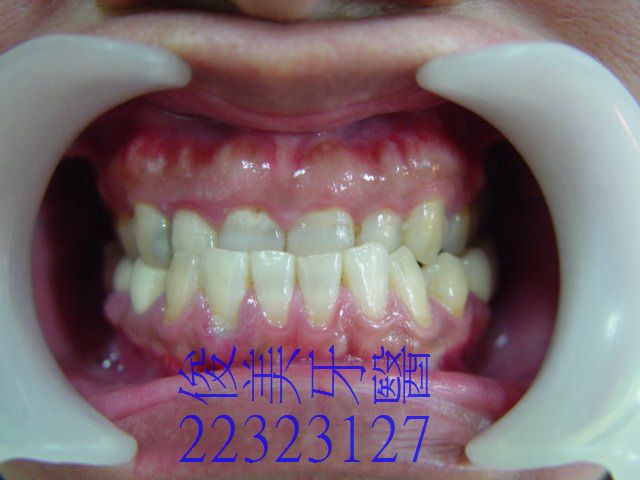

患者原始狀況,反咬,局部牙齦容易出血。

上排牙齒明顯被下排牙侷限住了。

牙齒移位導致牙縫易塞、紅腫。

治療前外觀。